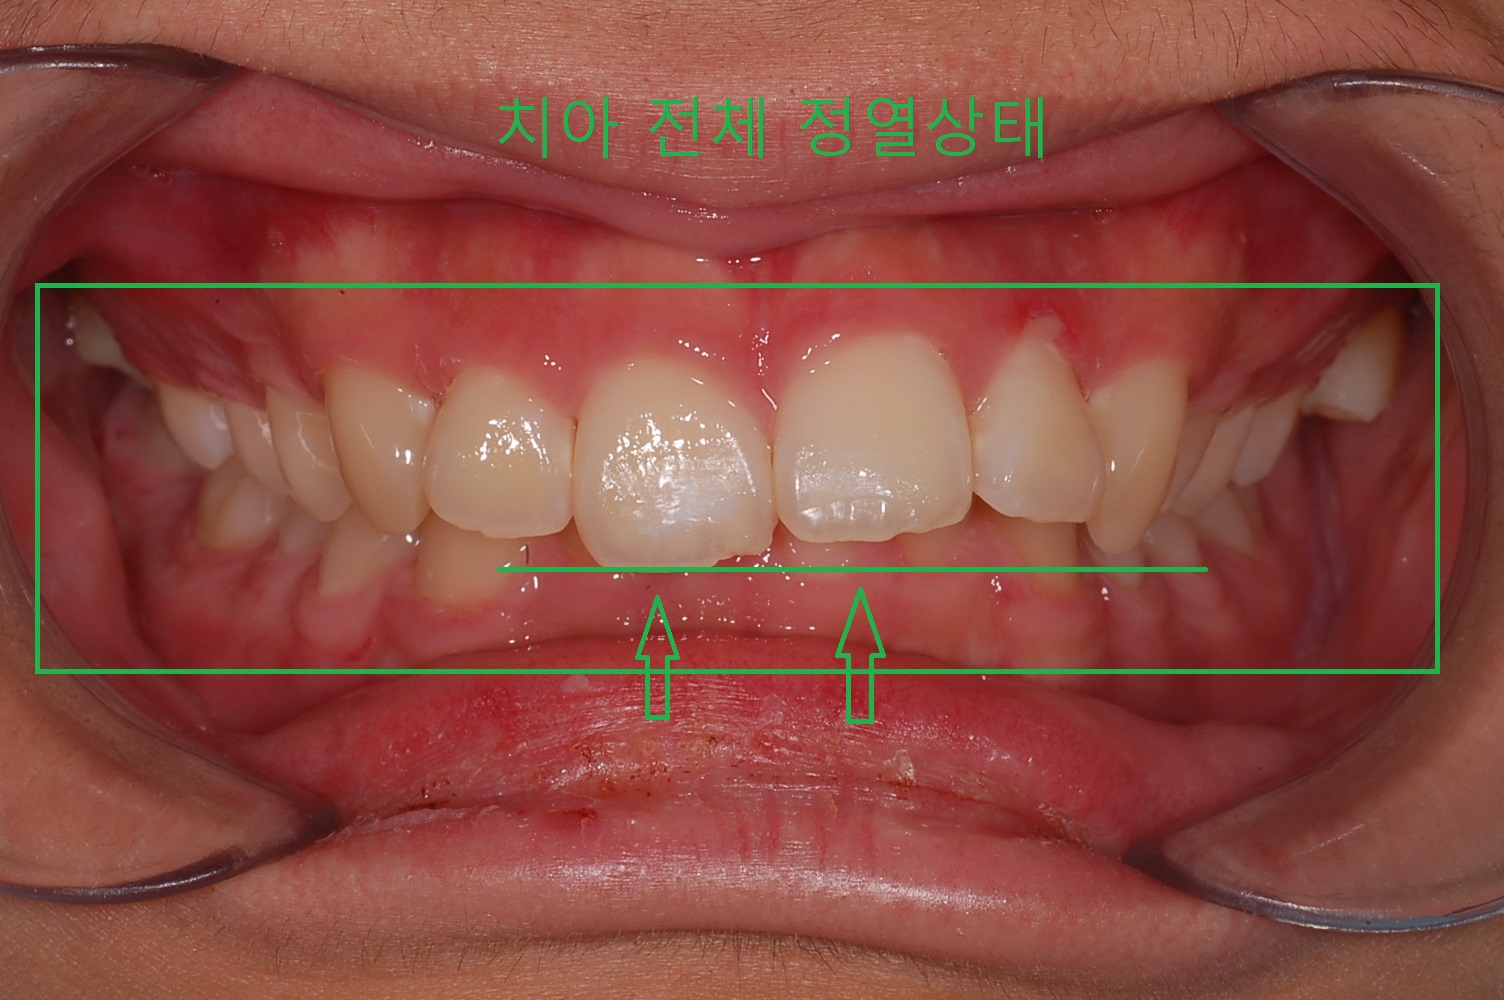

◎ 아들치아교정 전 상태확인 (과개교합사진)

- 「윗 앞니 과개교합」

전체적인 치아상태 및 배열 안면윤곽 상태 등 정밀검사를 실시하였으며 아들이 고등학생이어서 성장판 검사는 별도로 하지 않았습니다.

▼ 1차 정밀 검사 X-RAY

▼ 5개월 교정 후 사진(1)

▼ 5개월 교정후 사진(2)